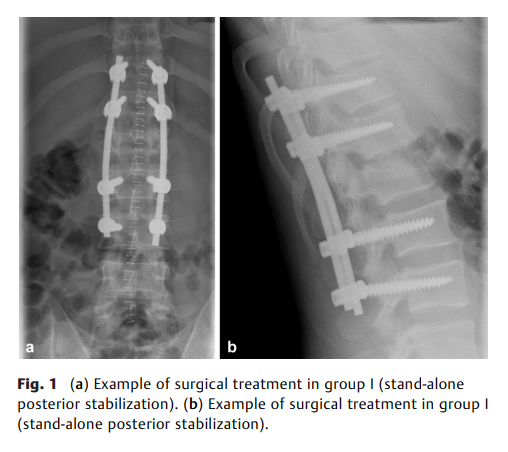

既往研究强调通过恢复矢状面序列和椎体高度来矫正脊柱骨折导致的畸形。本研究旨在比较创伤性胸椎或腰椎骨折手术治疗中,单纯后路稳定术(第一组)与后前路/联合入路(第二组)在影像学结果(包括矢状面指数和椎体高度丢失)方面的差异。